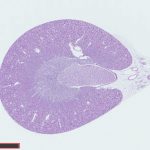

バーチャルスライドスキャナー【浜松ホトニクス社 NanoZoomer S210】を利用して、スライド標本のスキャン画像データを作製するサービスです。

ジェノスタッフ社にて作製したスライド標本のほか、お手持ちのスライド標本につきましてもバーチャルスライドの作製を承ります。

顕微鏡観察と同様に、標本の全体像から、細部の拡大像までパソコン上で自由自在に観察できます。

fig.1 画像の拡大と縮小

fig.3 スケール表示